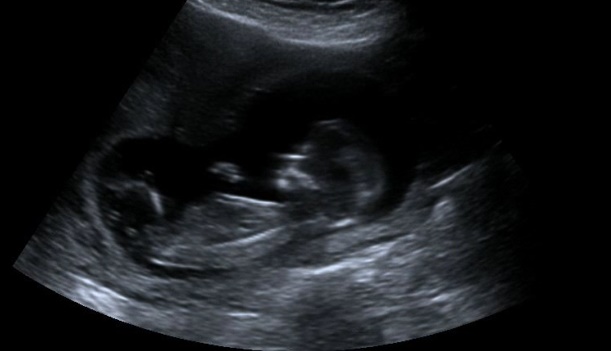

Is it sticking out too much for it to be a girly nub?

No one has confirmed on a boy but im just guessing, or am i wrong?

I would lean more towards girl from this pic.

I think boy. Cause it does seem to be on the rise.

I lean boy. But not 100%.

I lean girl:)